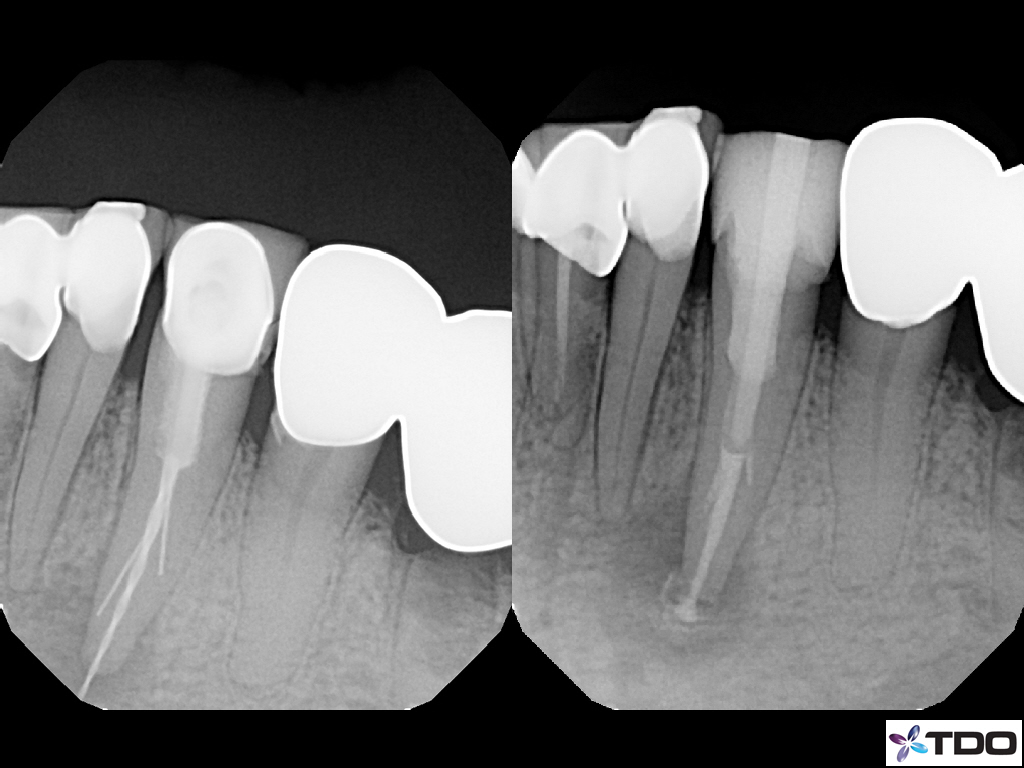

These cases show a level of commitment to conservative endodontics rarely seen in endo today. Plus the restorative excellence is inspiring and should stimulate all endodontists to up their game and help others realize how important the restorative aspect of endodontics is.